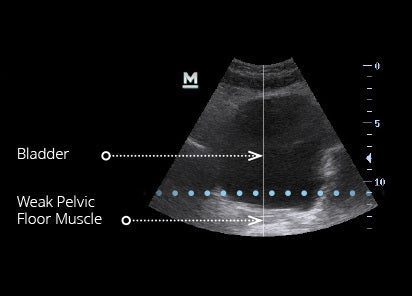

The Emsella Chair is a revolutionary, non-invasive treatment that uses high-intensity focused electromagnetic (HIFEM) technology to strengthen the pelvic floor muscles. One 28-minute session delivers the equivalent of over 11,000 Kegel exercises, helping improve bladder control, pelvic health, and overall confidence.

• Urinary leakage when coughing, sneezing, or exercising

• A weak pelvic floor after childbirth, surgery, or ageing